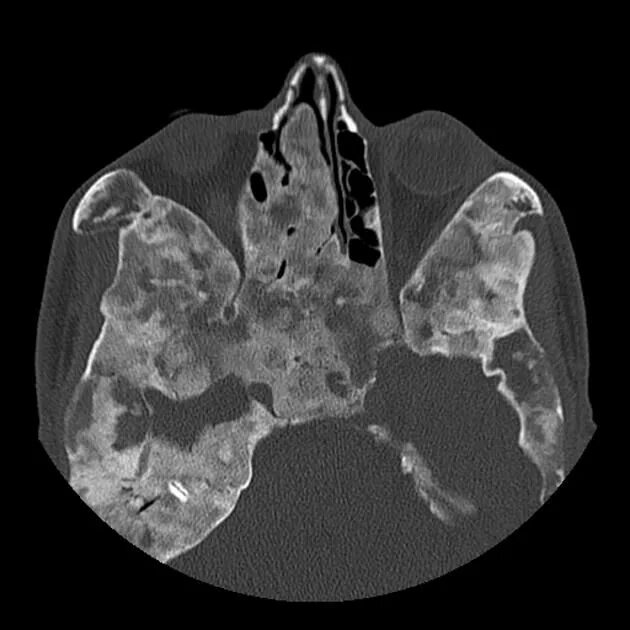

Череп на кт